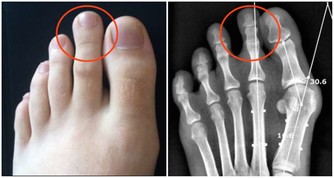

癌腫環狀生長者,導致腸腔縮窄,早期表現為糞柱變形、變細,晚期表現為不全性梗阻。

4、腫瘤浸潤及轉移症

大腸癌最常見的浸潤形式是局部侵犯,腫瘤侵及周圍組織或器官,造成相應的臨床症狀。

肛門失禁、下腹及腰骶部持續疼痛是直腸癌侵及骶神經叢所致。